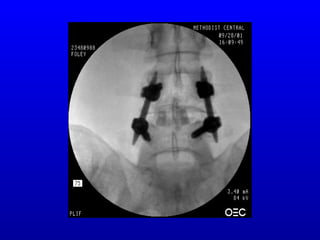

Minimally InvasiveMinimally Invasive LumbarFusion &Lumbar Fusion & Fixation with the SextantFixation with the Sextant Percutaneous PediclePercutaneous Pedicle Screw-Rod SystemScrew-Rod SystemSS

Sextant Rod InsertionSextantRod Insertion SystemSystem • MaterialsMaterials • Cannulated,Cannulated, Multi- AxialMulti- Axial ScrewsScrews • Rod ExtensionRod Extension SleevesSleeves • Rod InserterRod Inserter • Pre-contouredPre-contoured

Clinical ApplicationClinical Application Maybe used anytime pedicle fixationMay be used anytime pedicle fixation is felt to be necessary and/oris felt to be necessary and/or desirabledesirable Posterior supplementation for ALIF,Posterior supplementation for ALIF, minimally invasive PLIF, or minimallyminimally invasive PLIF, or minimally invasive TLIFinvasive TLIF Supplement to minimally invasiveSupplement to minimally invasive posterolateral fusionposterolateral fusion

Sextant Rod InsertionSextantRod Insertion ProcedureProcedure Initial incisionInitial incision

Sextant Rod InsertionSextantRod Insertion ProcedureProcedure Awl and probe pedicleAwl and probe pedicle Insert guide wiresInsert guide wires

Sextant Rod InsertionSextantRod Insertion ProcedureProcedure Insert screwsInsert screws

Sextant Rod InsertionSextantRod Insertion ProcedureProcedure Align screw extendersAlign screw extenders

Sextant Rod InsertionSextantRod Insertion ProcedureProcedure SelectSelect rod,rod, attach toattach to inserterinserter

Sextant Rod InsertionSextantRod Insertion ProcedureProcedure Rod insertion incision and pathRod insertion incision and path

Sextant Rod InsertionSextantRod Insertion ProcedureProcedure Insert rodInsert rod

Sextant Rod InsertionSextantRod Insertion ProcedureProcedure Tighten implantsTighten implants

Sextant Rod InsertionSextantRod Insertion ProcedureProcedure FinalFinal constructconstruct